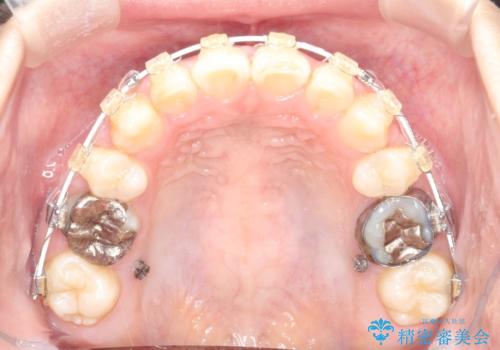

- 矯正装置

- 審美装置

- 前歯の凸凹を主訴に来院されました。

治療後は見た目だけでなく、噛みやすくなったと満足していただけました。